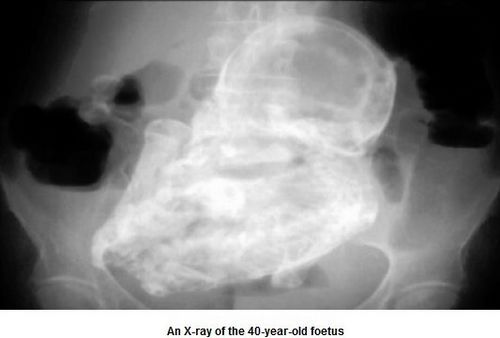

中新网2月14日电 据外媒13日报道,巴西一名84岁的妇女近日腹痛就医,经X光检测发现,她肚子里有一个已经石化的胎儿。石胎留在她腹中已经长达44年。

医生们通过X光透视妇女的腹部,才吃惊地发现妇女肚子里有一个已经变成化石的胎儿,医生以大小估算胎儿应该是20到28周大的时候死亡。

经X光透视,胎儿的头、四肢、肋骨和脊椎都清晰可见。医生说,四十多年来,死胎没有让这名妇女的健康出大问题,真是个奇迹。

无独有偶,哥伦比亚首都波哥大日前也发生妇女怀石胎的怪事。2013年12月8日,一名82岁的老妇因腹痛就医,医师惊讶地发现,造成她腹痛的原因,竟是一个已形成40年的“石胎”。